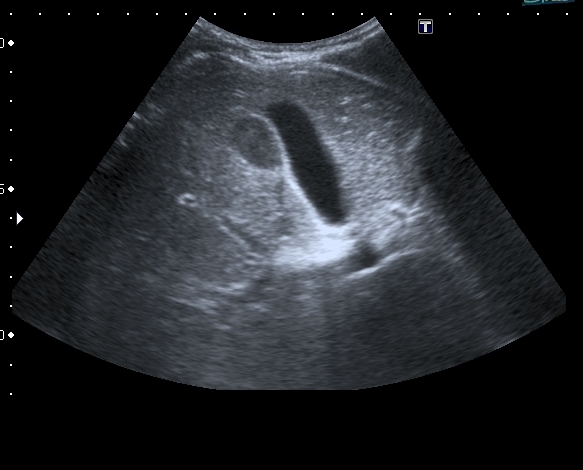

На УЗИ рядом с желчным пузырём определяется овоидное образование солидной струкутры с чёткими контурами.

Порекомендовал КТ, но в связи с наступающими новогодними праздниками и каникулами мальчик уехал домой и появился повторно через 2 месяца без жалоб для контрольного исследования. На УЗИ - картина осталась без динамики

Предположил наличие удвоения желчного пузыря, с этим заключением пациент исчез из поля зрения.